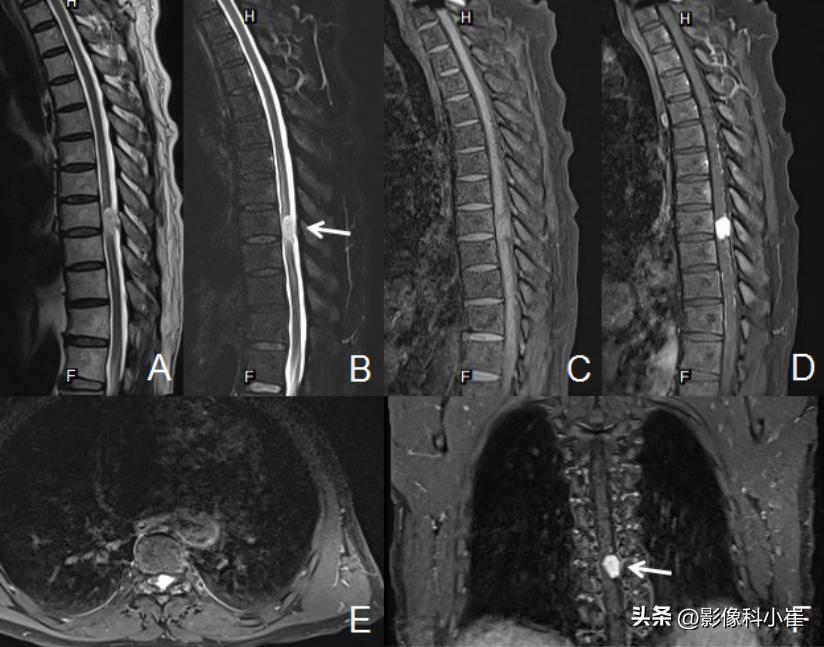

T8椎体水平椎管内脊髓外见不规则形等T1(图C)长短T2(图A)异常信号灶,FS-T2WI(图B)示高信号,大小约2.0×1.2cm,增强后呈均匀明显强化,脊髓受压向右前移位,病灶上下缘蛛网膜下腔增宽,T6-10椎体水平脊髓内见片状长T2异常信号,提示脊髓受压水肿。